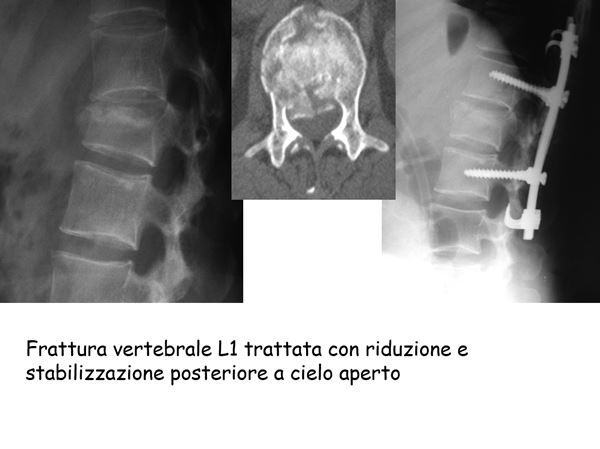

frattura vertebrale L1